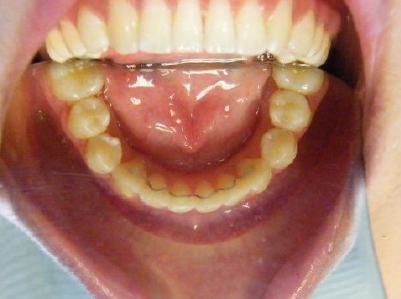

Patient 4: Upper and lower crowding and a deep overbite.